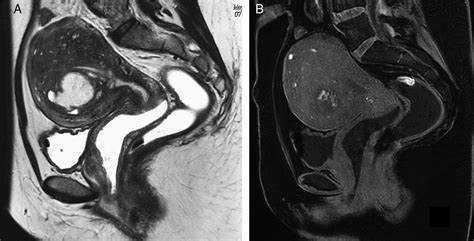

La resonancia magnética (RM), con una técnica de exploración e interpretación cuidadosas, ofrece un diagnóstico y estadificación más precisos que la ecografía, particularmente en la endometriosis pélvica profunda. La RM puede identificar implantes en localizaciones de difícil acceso para exploraciones endoscópicas o laparoscópicas.

La sintomatología es variable, y el diagnóstico puede retrasarse significativamente. Los quistes endometriósicos ováricos (endometriomas) se diagnostican bien por ecografía, pero la RM ofrece una semiología más específica: quistes con contenido hiperintenso en T1 y oscurecimiento ("shading") en T2.

La endometriosis pélvica profunda, definida como afectación de al menos 5 mm por debajo de la superficie peritoneal, se asocia frecuentemente a dolor pélvico y dificultad reproductiva. Los implantes profundos pueden ser sutiles en RM, predominando el componente fibroso.

La técnica de RM para la evaluación de endometriosis pélvica requiere secuencias potenciadas en T2 y T1, con y sin supresión grasa, para detectar implantes y focos hemorrágicos. La exploración puede realizarse en cualquier día del ciclo menstrual, aunque la fase del ciclo puede ayudar en la interpretación.

La afectación del útero por endometriosis puede deberse a implantes peritoneales que infiltran el miometrio (adenomiosis). La adenomiosis en RM se manifiesta como un engrosamiento de la zona de unión miometrial, con posibles focos glandulares o hemorrágicos.